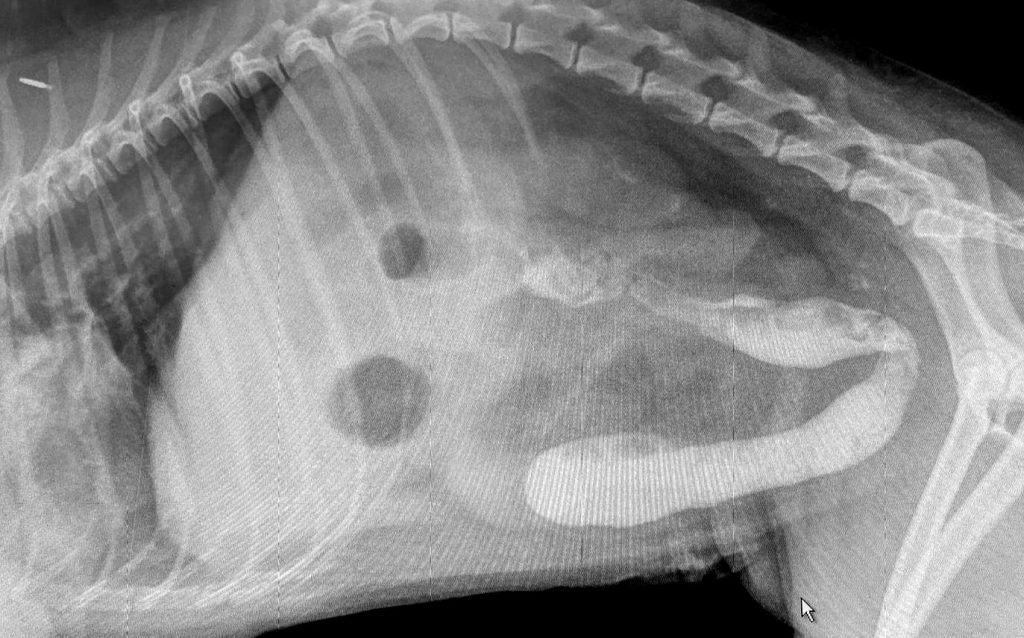

Sand ingestion in three dogs a cause of severe gastroenteritis (even Drain Cleaner Ingestion In Dogs This article decodes common ingredients in cleaners to help you better understand the potential toxic risk for pets and your treatment. Household cleaners can include toilet bowl cleaner, pine oil, drain cleaner, rust and calcium removers, and disinfectants. When you take the dog to the clinic or emergency hospital, your veterinarian may induce vomiting, or the stomach may be. Effects. Drain Cleaner Ingestion In Dogs.